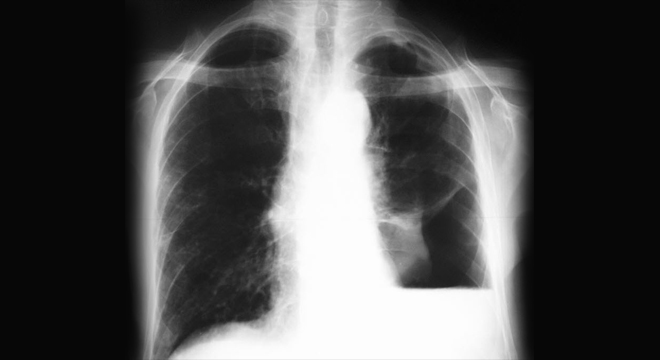

Pneumothorax: Röntgenbild des Brustkorbs

• Sicherung der Diagnose auf dem Röntgenbild des Brustkorbs (Thorax)